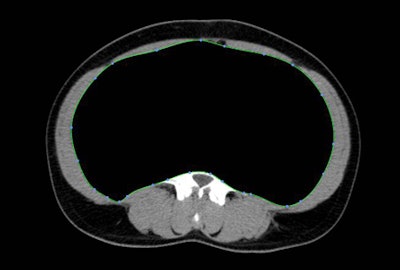

![]() |

| When gender was ignored (chart above), patients on 6-MP had significantly less SAT overall, while patients on IFX had less VAT/SAT. Results segregated by gender (chart below) showed significant differences between genders for upper gastrointestinal disease, perianal disease, and IFX use. Significant differences were all found in female patients, and the chart also shows that patients with markers of severe disease have less VAT. |